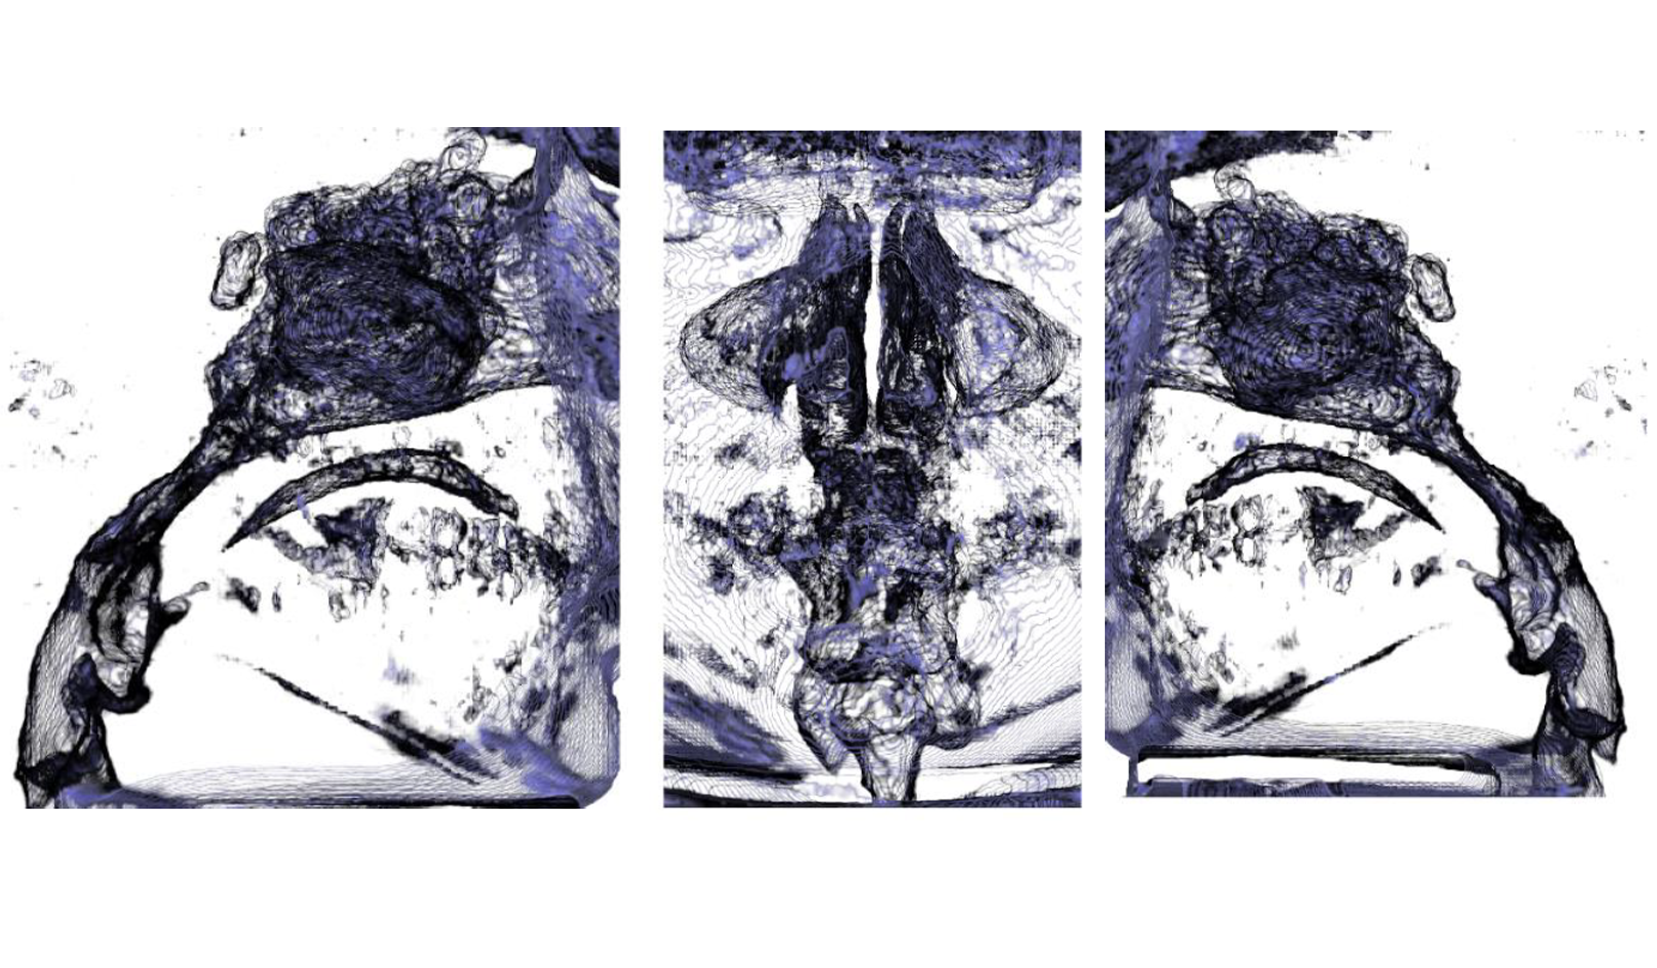

Senos Paranasales

Oido

Articulación Témporo Mandibular (ATM)

Cadena Osicular DER IZQ

Oído Interno (Cóclea y Canales Semicirculares) DER IZQ